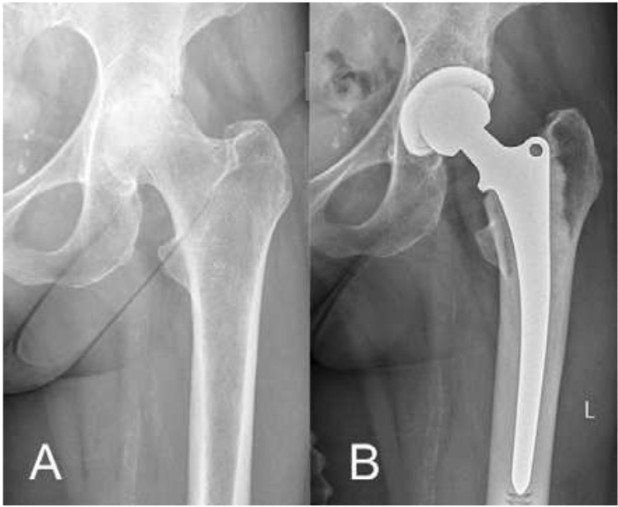

Fall 1

74-jährige Patientin mit RA-bedingter Hüftgelenksarthrose (Abb.4): Kompletter Gelenkspaltverlust sowie relativ weite Markraumhöhle (Bild A). Postoperatives Röntgenbild nach sechs Monaten (Bild B). Aufgrund der Knochenqualität wurde der Patientin eine Hybrid-Hüftprothese (Kombination aus zementfreier und zementierter Prothese) über einen minimalinvasiven Zugang mit zementfreier Pfanne und Femurschaftprothese in zementierter Technik im Knochen verankert. War die Patientin vor der Operation im Alltag massiv eingeschränkt und konnte kaum noch schlafen, ist sie heute wieder schmerzfrei und agil. Aus Angst vor einer Operation hatte sie sehr lange zugewartet, was sie im Nachhinein angesichts des hervorragenden Resultates bereut.